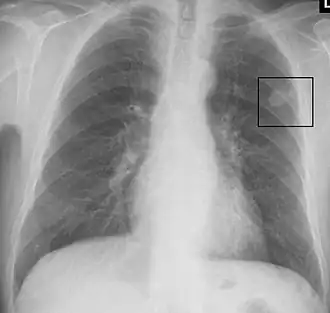

- Рак верхушки лёгкого с синдромом Панкоста

- Рак лёгкого